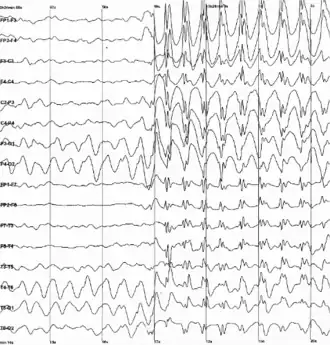

| Descargas generalizadas de ponta-onda num electroencefalograma | |

Uma vez que se suspeite de epilepsia, o eletroencefalograma (EEG) pode ser utilizado para apoiar o diagnóstico, classificar os tipos de crise e identificar síndromes epilépticas. O EEG de rotina pode incluir técnicas de ativação como hiperventilação ou estimulação fotossensível. No entanto, um EEG normal não exclui o diagnóstico de epilepsia. Quando os achados iniciais são inconclusivos, podem ser considerados exames como EEG com privação de sono, EEG ambulatorial ou monitoramento prolongado com vídeo-EEG.[80]